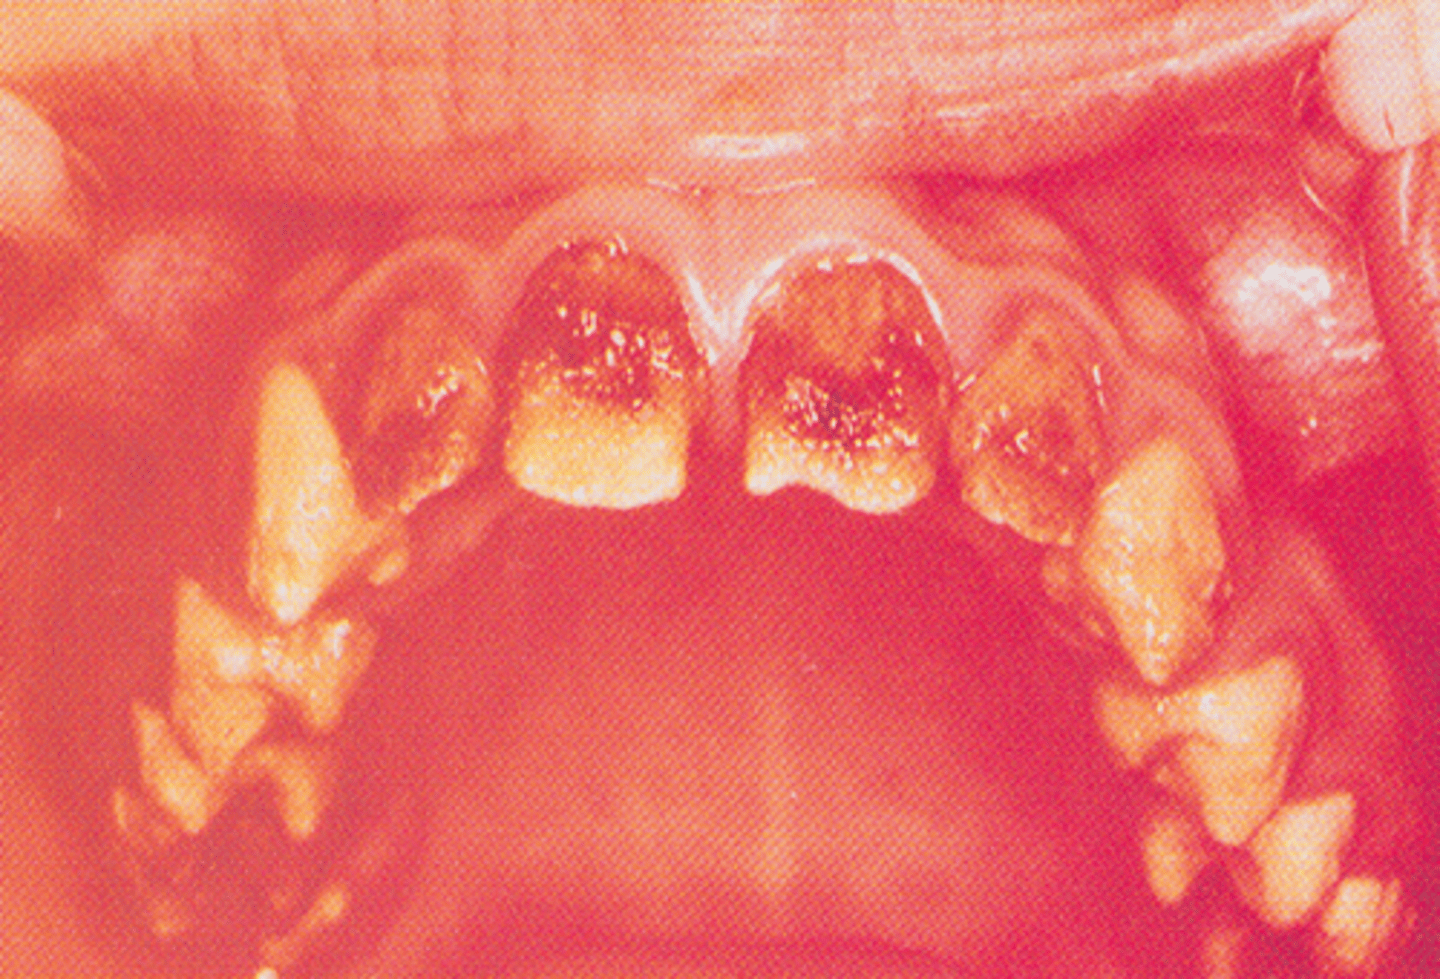

Type I: Hypoplastic amelogenesis imperfecta

1. The tooth enamel does not develop to a normal thickness

2. Autosomal dominant and autosomal recessive

Type II: Hypocalcified amelogenesis imperfecta

Normal thickness but poorly calcified

Type IV: Hypoplastic-hypomaturation amelogenesis imperfecta

1. Associated with taurodontic teeth

2. Yellow to brown pitted enamel